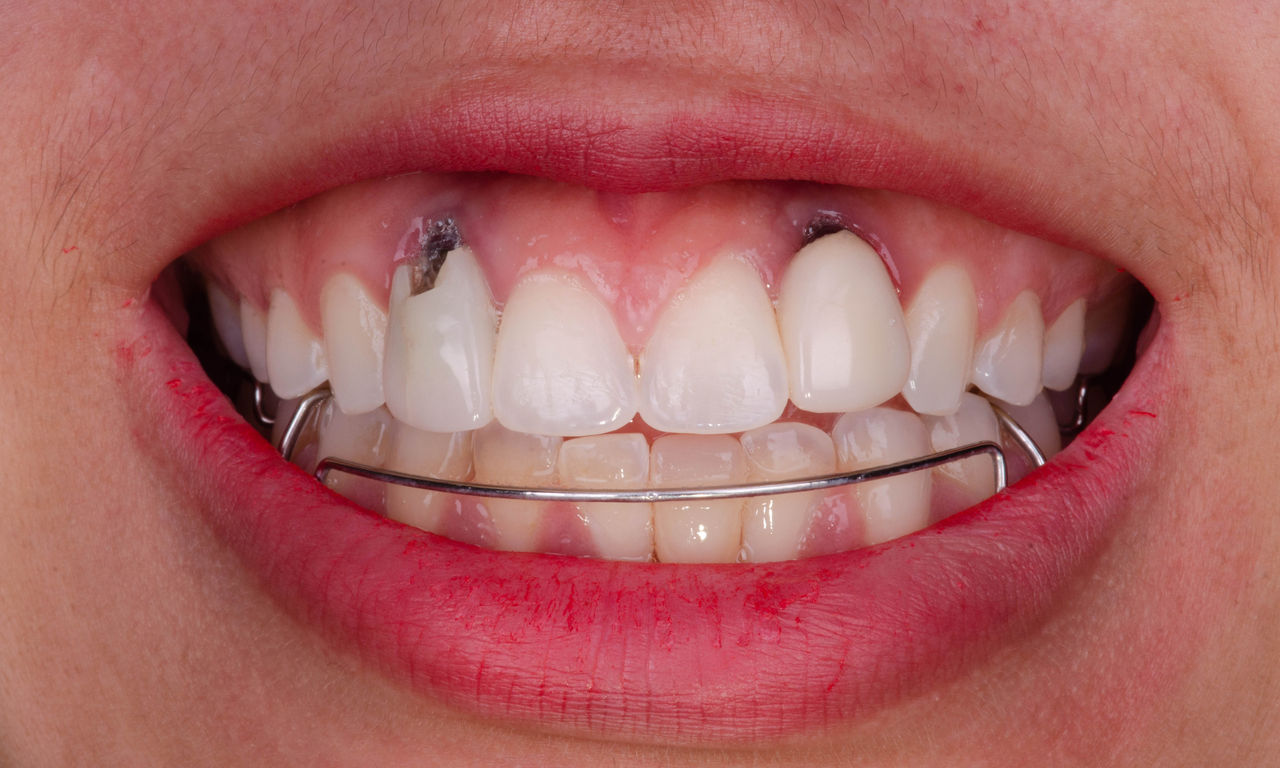

Upper central incisors, in 4 hours

Four IPS e.max CAD single crowns

The restoration with all-ceramic crowns did not require subgingival preparation to cover the margin and no dark metal shadows disturbed the aesthetics. With CEREC Primescan and CEREC Primemill patients receive a high-quality all-ceramic restoration faster than ever before.

Before: Inadequate fillings on teeth 12-22, an uneven gingival line on 12 and 11 and incisal edges severely eroded.

After: Four highly aesthetic and individualised lithium disilicate ceramic crowns.

Claudia Scholz

Kiel, Germany